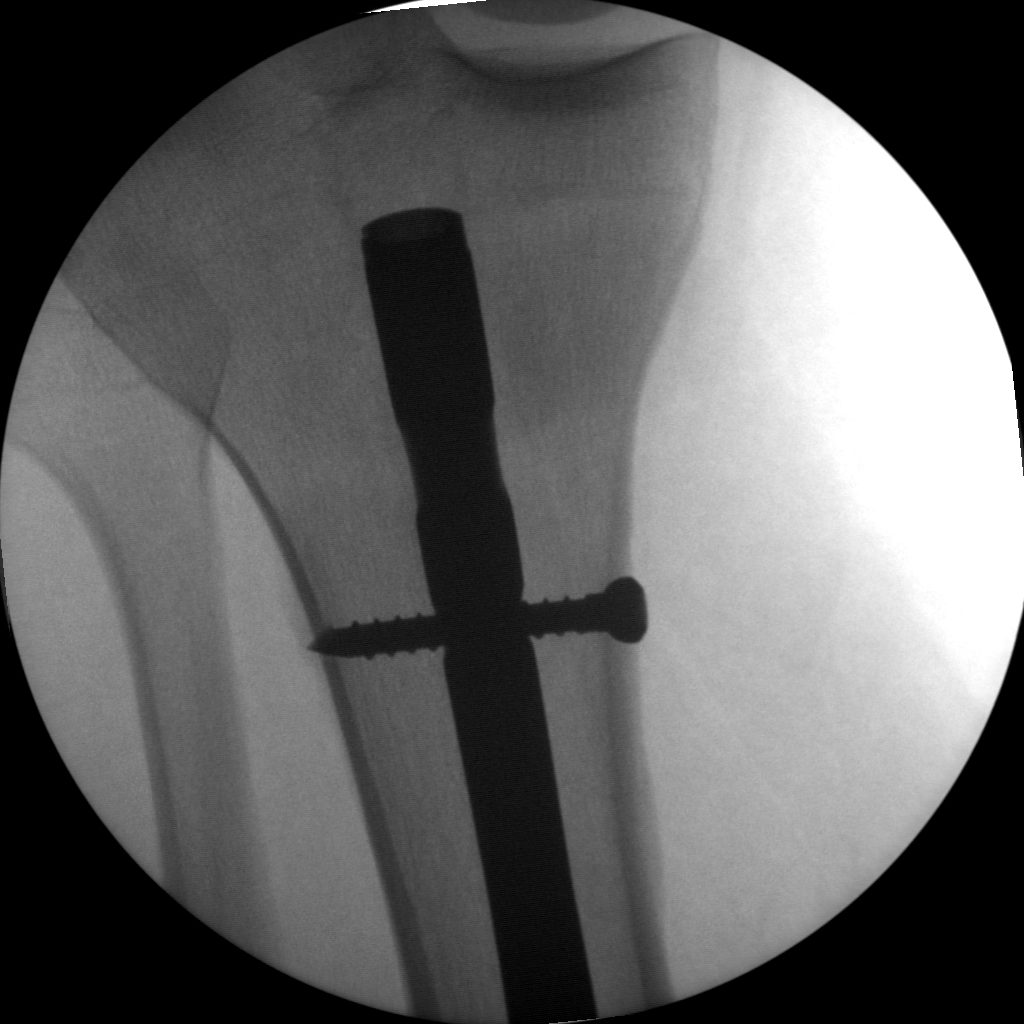

Skan-C plays a critical role in orthopaedic procedures, providing excellent imaging during interventional procedures, and allowing for precise localization and accurate treatment. The ability of Skan-C to offer dynamic visualization of visualization structures enhances patient safety, minimizes complications, and improves the overall effectiveness of orthopedic interventions.

Long bone nailing

Clinical Evidence

Skan-C is a great C-arm for orthopaedic treatments for several reasons